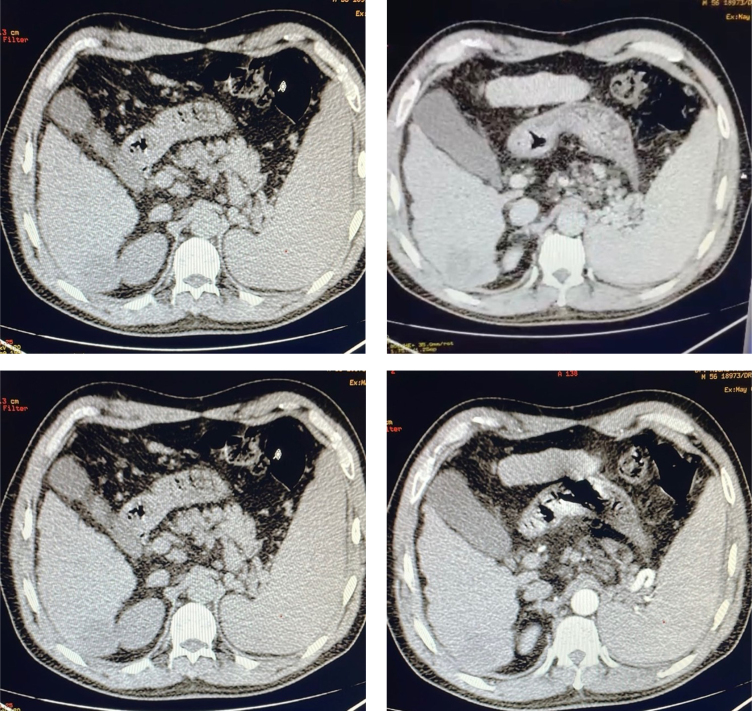

Case report: A 56-year-old male with chronic hepatitis C, presenting pain in the right hypochondrium. Imaging revealed a solitary liver lesion, subsequently resected and histologically diagnosed as HCC. Macroscopic examination found a 4×4 cm encapsulated liver nodule with necrotic areas, surrounded by numerous smaller satellite nodules in Segment 6. The liver was in micronodular cirrhosis. Histologically, the tumor had focal trabecular or pseudoglandular patterns within a vascularized stroma. The cells were large, with clear to eosinophilic cytoplasm and hyperchromatic and pleomorphic nuclei with focal anaplastic features. No vascular invasion was noted in adjacent cirrhotic liver tissue.

Results: The final diagnosis was CHCC. Due to its rarity and overlapping characteristics with other hepatic tumors, CHCC poses diagnostic challenges. Accurate diagnosis necessitates thorough histopathological assessment and molecular testing. The identification of the alternative lengthening of telomeres phenotype may distinguish CHCC from conventional HCC and hold potential implications for targeted therapeutic approaches.